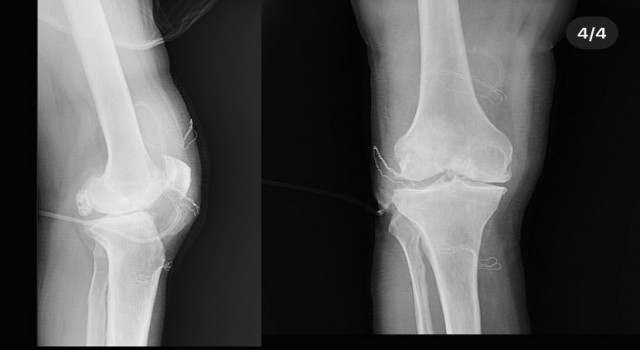

Dizden çıkan eklem fareleri şaşırttı

Diz ağrısı şikayeti ile geldiği Düzce Üniversitesi Tıp Fakültesi Hastanesi’nde ameliyata alınan hastanın dizlerinden toplam 41 adet multipl sinovial kondromatozisi çıkartıldı. Özellikle diz eklemi çevresinde görülmekle birlikte kalça, dirsek ve diğer eklemlerde de görülen, ufak parçalardan oluşan cisimler olarak tanımlanan eklem faresi, eklem çevresinde eklem sıvısı ya da sinoviyumda görülen kıkırdak ya da kemik parçalarıdır. Eklem farelerinin boyutları birkaç milimetreden birkaç santimetreye kadar çıkabiliyor.

Düzce Üniversitesi Tıp Fakültesi Hastanesi Ortopedi ve Travmatoloji Kliniği’nde başarılı geçen operasyonu; Doç. Dr. Zekeriya Okan Karaduman, Doç. Dr. Mehmet Arıcan ve Dr. Öğr. Üyesi Sönmez Sağlam gerçekleştirdi.